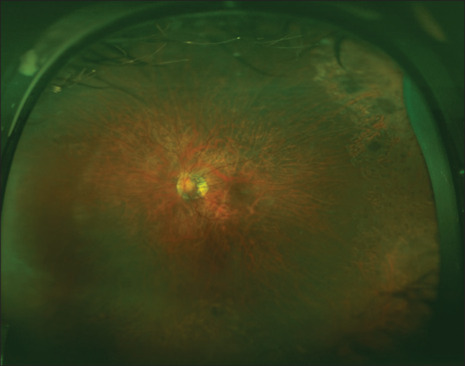

本病例报告了一名因 LRPAP1 基因同源变异而患有高度近视的儿童出现的眼窝裂伤。一名 9 岁女孩因 LRPAP1 基因同源突变而患有高度近视,右眼曾进行过视网膜脱离修复手术。裂孔病变演变为片状黄斑孔,需要进行玻璃体切除术。术后病情稳定。隐性 LRPAP1 致病变体可能会在儿童期出现近视性黄斑裂孔。需要进行长期随访,以确定早发近视眼窝沟封闭的自然史。

This case reports the development of foveoschisis in a child with high myopia due to a homozygous LRPAP1 pathogenic variant. A 9-year-old girl with high myopia due to a homozygous mutation in the LRPAP1 gene and a history of retinal detachment repair in her right eye, presented on follow-up with progressive myopic foveoschisis in the left eye noted on optical coherence tomography. The schitic changes evolved into a lamellar macular hole and required vitrectomy. Postoperatively, stabilization of the condition was achieved. Myopic foveoschisis could develop in childhood in the setting of recessive LRPAP1 pathogenic variants. Long_term follow-up is needed to determine the natural history of early-onset myopic foveoschisis.